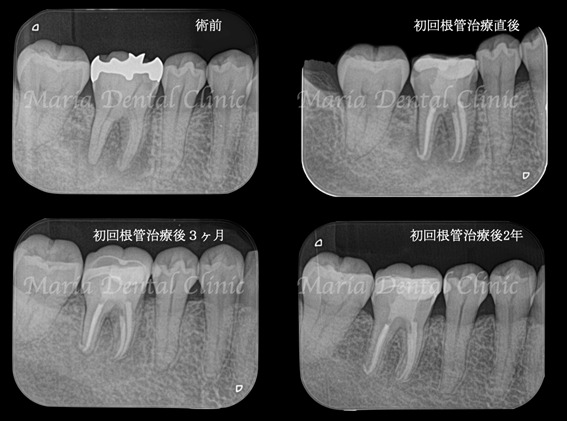

精密根管治療、初回根管治療の成功率は、歯髄壊死の場合80%〜90%とされており、注意深く予後観察を行なっていく必要があります。

今回は初回根管治療終了後の3ヶ月で骨の再生が始まり、2年後には病変は完全に無くなるまでに回復しました(画像①)。